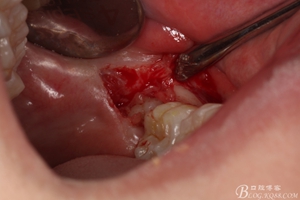

圖10. 翻開瓣。38牙冠還有部分骨質(zhì)覆蓋,遂用高速牙鉆去骨

圖11.去骨---暴露出38的牙冠最大周徑